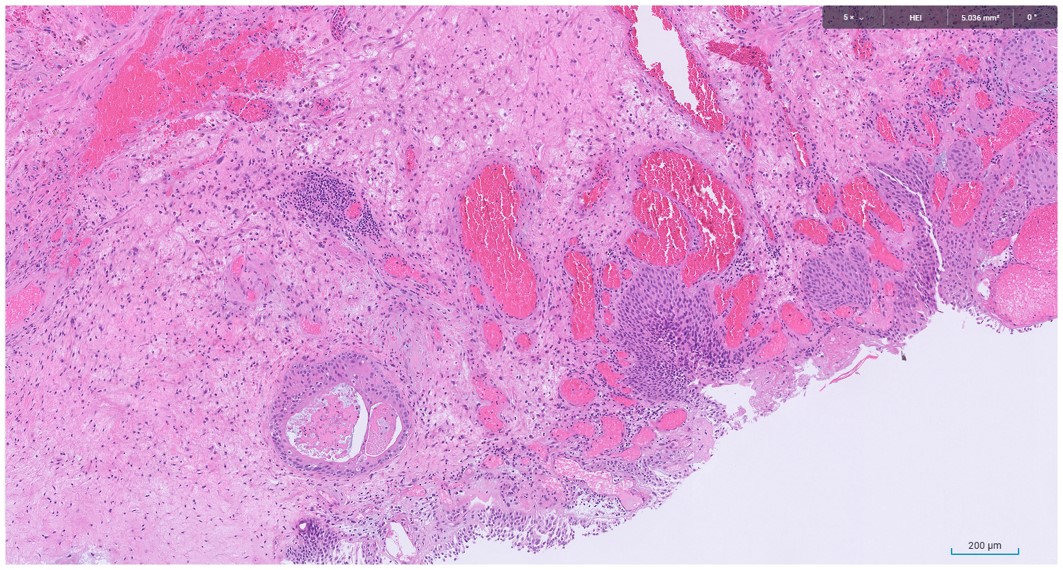

Microscopic image possibly detecting cancerous areas in human tissue

What is the most likely diagnosis?

1. Radiation cystitis

2. Cystitis cystica

3. Invasive urothelial carcinoma

4. carcinoma in situ

Radiation cystitis